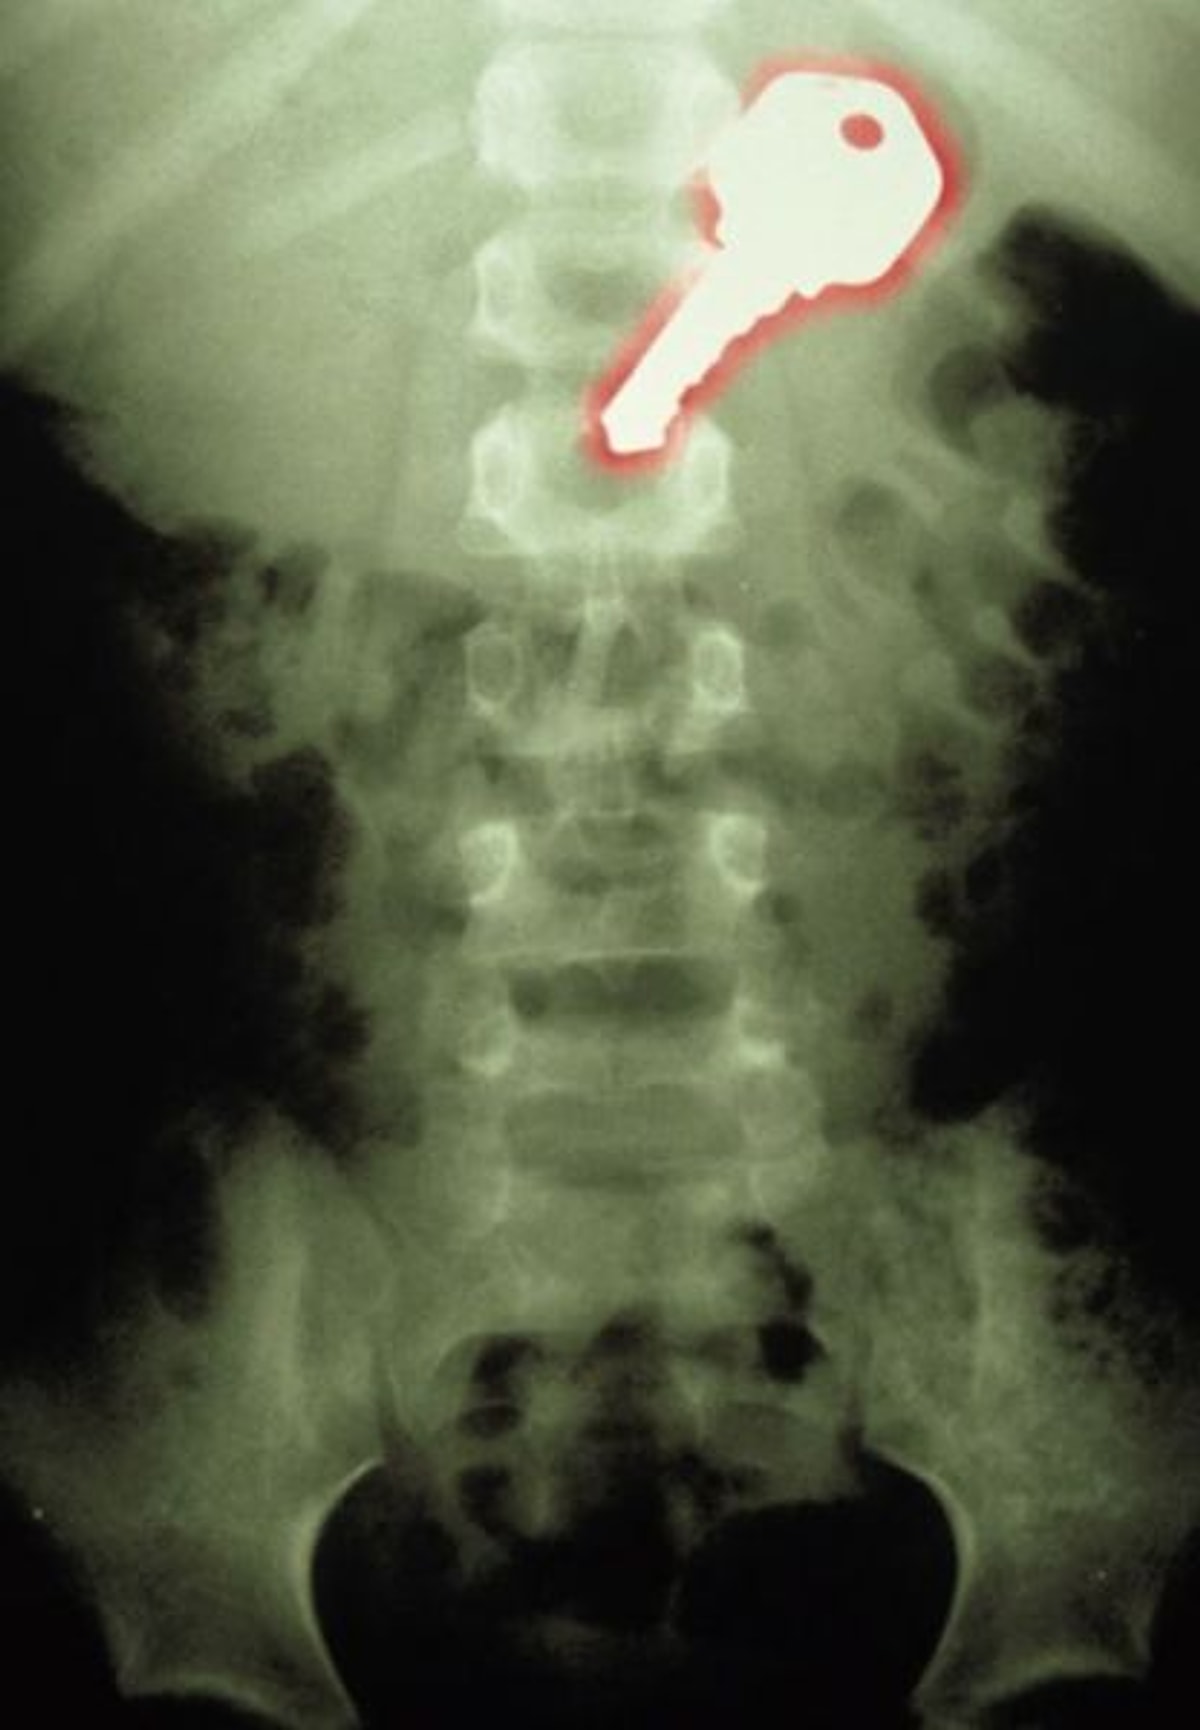

Удаление инородных тел из кишечника

Удаление инородных тел из кишечника 115 фотографий